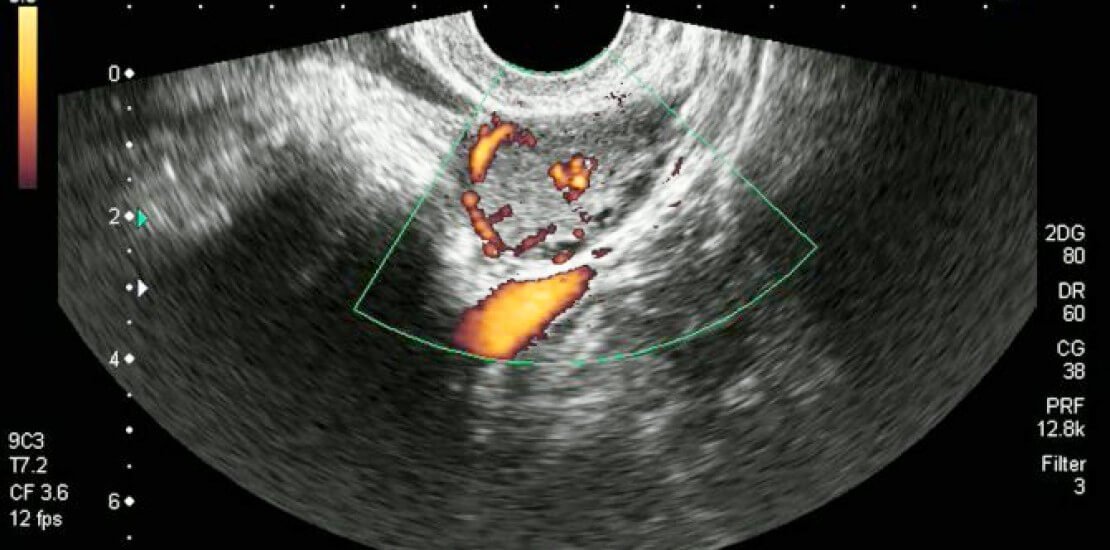

Як перевірити функціональність жовтого тіла?

Іноді наявність або відсутність проблем з жовтим тілом може бути діагностовано різними методами:

- УЗД яєчників